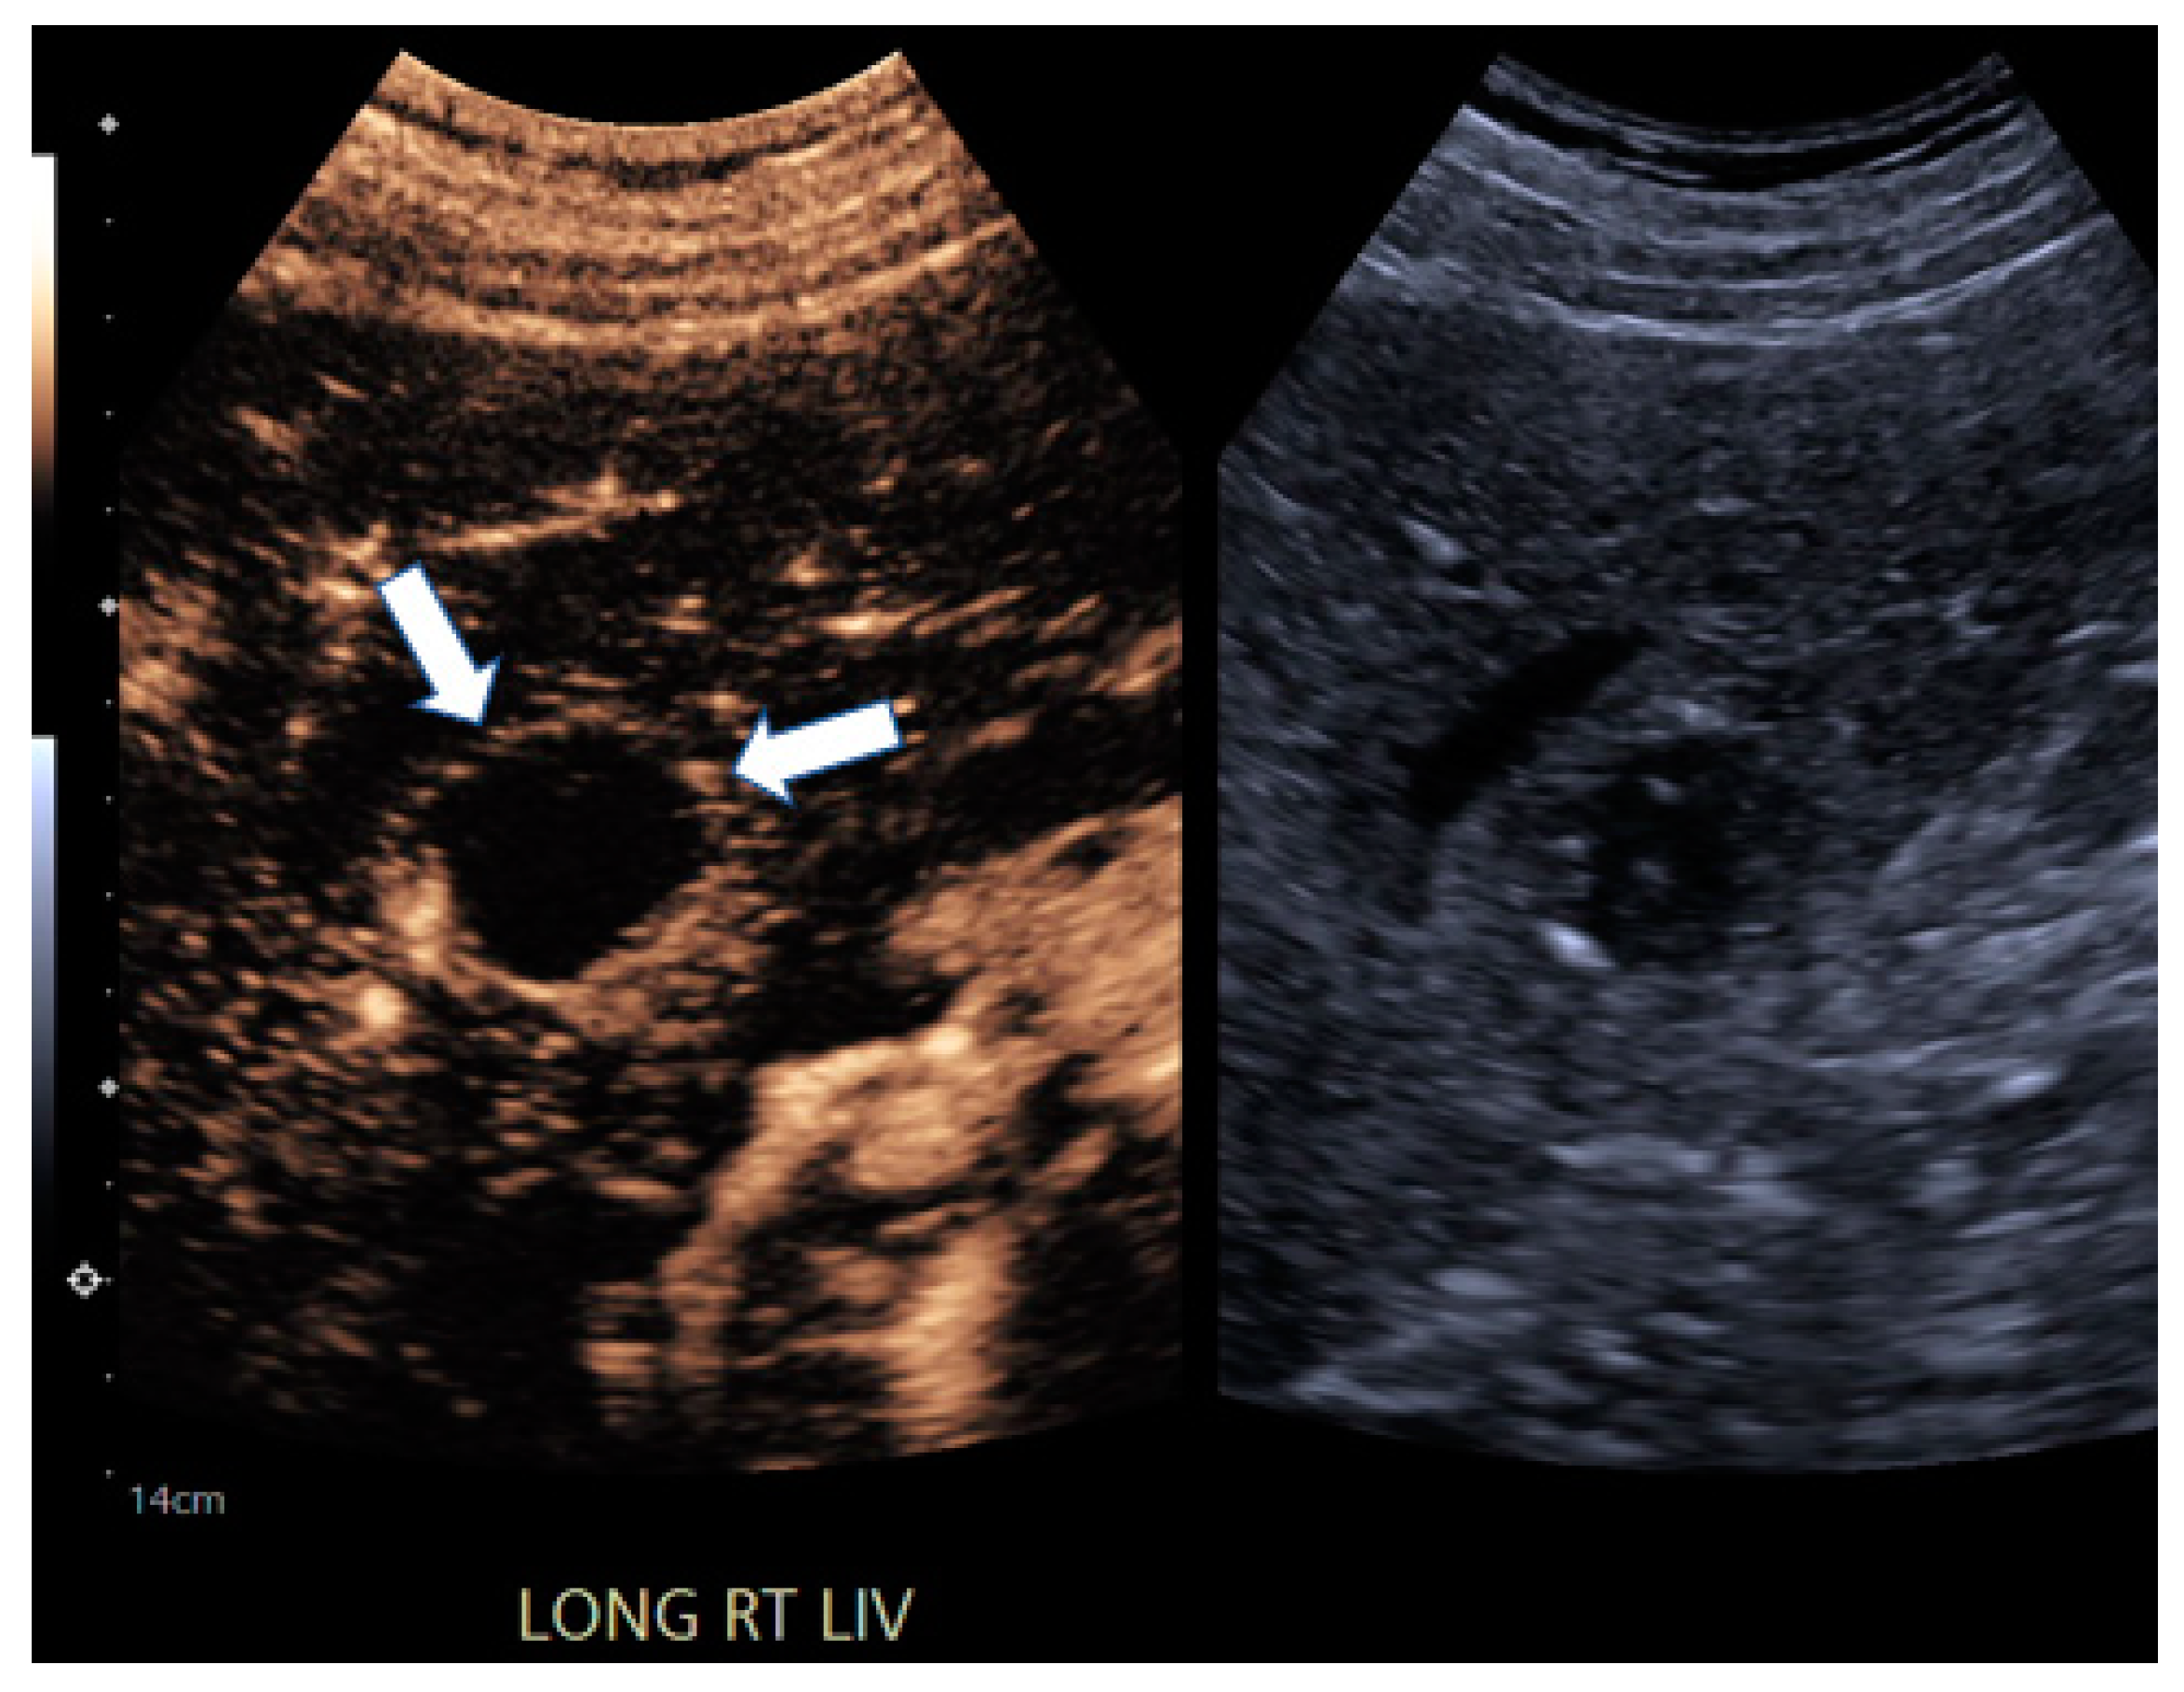

| 6 | CEUS | Target | LR-viable | CT missed subtle disease at the periphery of the treated HCC (Figure 2) |